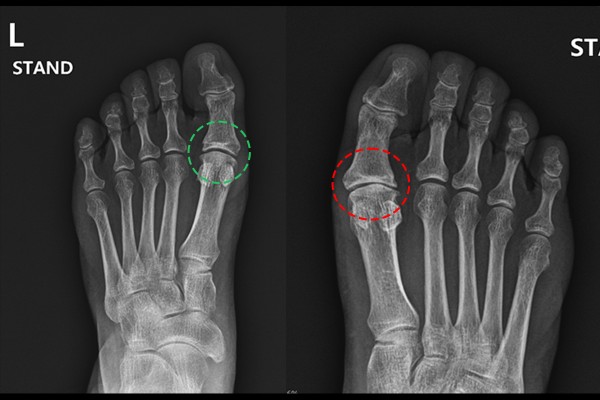

환자분의 발 상태를 확인하기 위해 X-RAY 촬영을 진행하였고, 정상적인 좌측 발과 비교했을 때, 우측 발 엄지 관절이 좁아져 있는 것이 확인되었습니다.

MRI를 확인했을 때 엄지발가락 쪽에서 골부종이 확인되어 무지강직증[엄지관절염](Hallux rigidus foot Rt.)을 진단하였습니다.